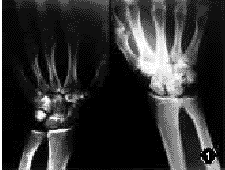

检查:左腕部肿胀,腕掌尺侧可见1cm长不规则的伤口流血,未触及豌豆骨但压痛明显。消毒后,用手指经伤口沿尺侧到背侧可探及皮下隧道。左腕背部可扪及0.6cm×0.6cm大小的硬结,有压痛并可在皮下活动。左手指痛觉存在,手指屈伸功能存在,腕关节活动部分受限。双侧腕关节正侧位X线片示:左豌豆骨背侧脱位,左三角骨骨折(图1,2)。诊断:左豌豆骨背侧脱位,左三角骨开放性骨折,左尺神经掌侧支挫伤。

图1双侧腕关节正位X线片

图2双侧腕关节侧位X线片